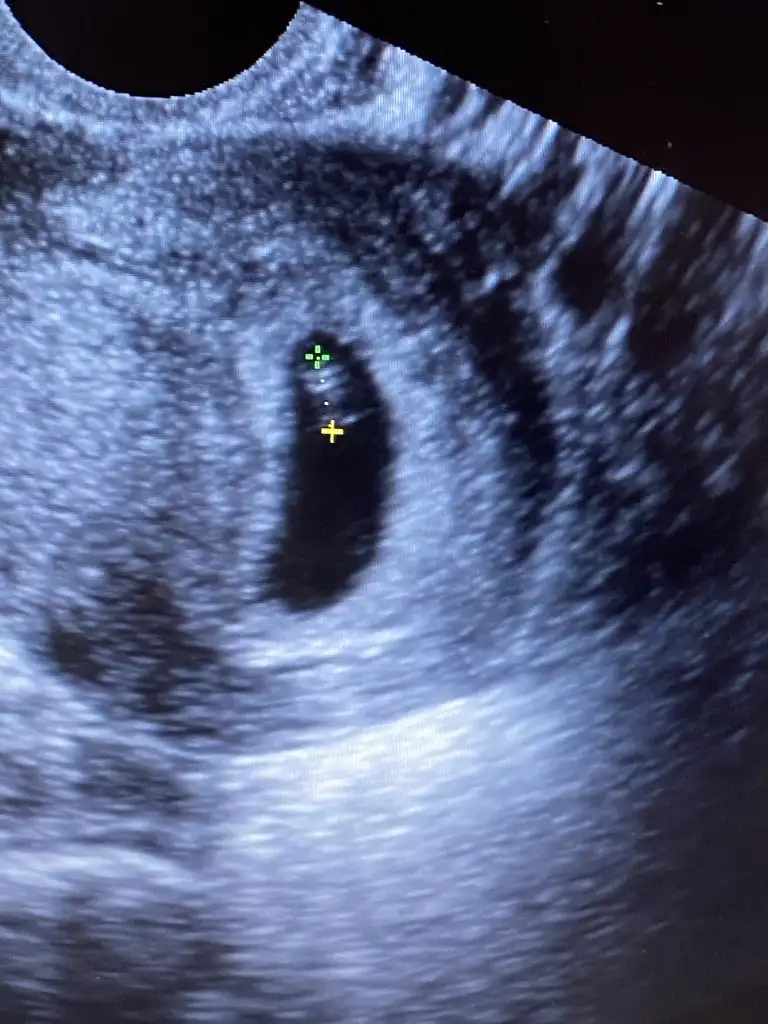

Arkadaslar 2 ultrason fotosu ekliyorum ikiside benim 3 gun arayla ikiside karından ultrasonla bakıldı cok merak ediyorum biri sağda biri solda🤣